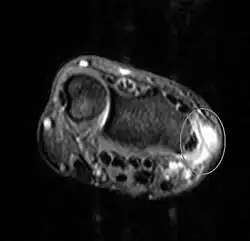

Die chronischen Formen machen sich zum Teil nur durch knotige Verdickungen der betroffenen Sehne bemerkbar, teilweise mit schmerzhaftem, tastbarem „Knirschen“ und Reiben der Sehne. Dadurch kann es zum Phänomen der so genannten schnellenden Finger (Tendovaginitis stenosans = einengende Sehnenscheidenentzündung) kommen: Dabei steckt die verdickte Sehne zunächst in der Sehnenscheide fest, bei stärkerem Muskelzug gleitet sie dann plötzlich aus der Verengung heraus (vor allem bei Extensionsbewegungen). In der Schweiz wird dazu auch „Spickfinger“ gesagt.

Eine Sonderform der Sehnenscheidenentzündung stellt die Tendovaginitis stenosans de Quervain (Quervain-Krankheit) dar, die das erste Sehnenfach der Hand betrifft. Durch dieses verlaufen die Sehnen der Daumenmuskeln Musculus abductor pollicis longus und Musculus extensor pollicis brevis. Ursache ist meist eine Überlastung dieser Sehnen durch häufige Abduktion (Bewegung des Daumens von der Handfläche weg) und Veranlagung. Ein gehäuftes Auftreten wird bei Menschen beobachtet, die häufig mit kraftvoller Daumenabspreizung ein Baby halten, sowie häufigem Tippen von Mobiltelefonnachrichten.